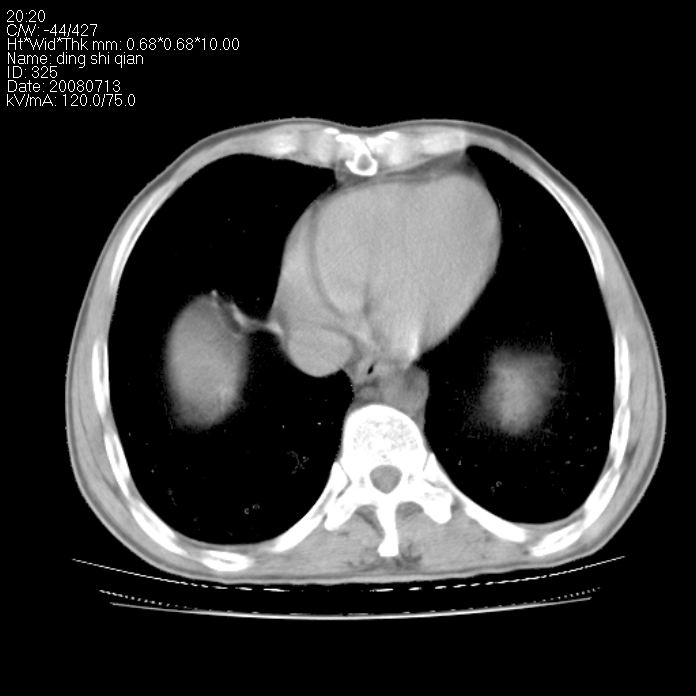

标题: CT14654:男 50岁 近来胸痛 [打印本页]

标题: CT14654:男 50岁 近来胸痛

右侧上肺块状软组织影,浅分叶,边缘毛刺证,与胸膜粘连,考虑:周围性肺癌

右肺上叶周围型肺癌可能性大。

右侧上肺块状软组织影,浅分叶,边缘毛刺证,与胸膜粘连,考虑:周围性肺癌!支持!

典型右肺周围型肺癌

右肺上叶周围型肺癌。